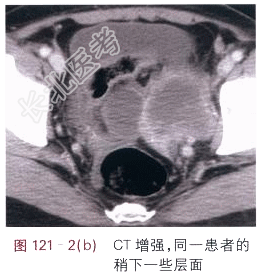

- [材料题] 患者,女,44岁,发现腹部包块2月余。体格检查:未见阳性体征。影像学资料如图121-1~图121-3所示。

- 简答题1、请叙述卵巢癌临床症状和该影像学表现?